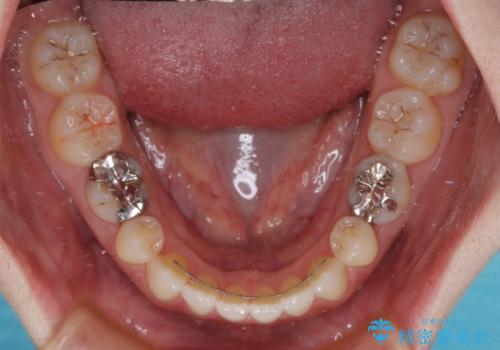

すきっ歯をインビザラインできれいな歯並びに改善

- 1年5ヶ月

すきっ歯の原因は色々ありますが、嚥下や発音時の舌突出癖が大きな原因となることがあります。

こちらの患者様も強い突出癖があったため、舌のトレーニング指導を行いました。